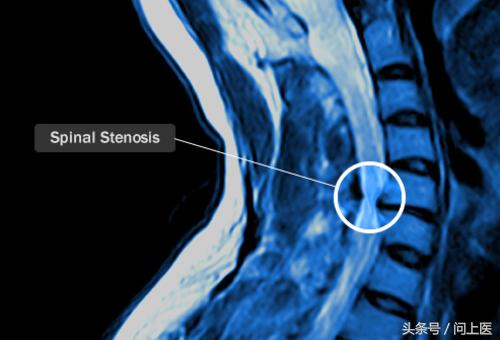

7. 椎管狭窄

椎管狭窄是颈部上脊椎管变窄引起的,它会压迫脊椎,使患者手臂、腿部或脖子感到疼痛、无力、麻木。椎管狭窄是一种退行性疾病,在中老年人群中较常见。关节炎、癌症、遗传性疾病等疾病,都可能导致椎管狭窄。

椎管狭窄如何治疗?

日常生活中应尽量避免颈部和头部受伤。椎管狭窄的治疗方法包括药物治疗、理疗和手术。